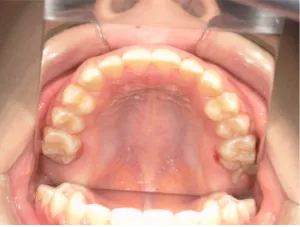

治療中③中1:非抜歯治療の診断で、上顎に歯の生えるスペースをつくるため上顎左右6をプレートで遠心移動し、隙間ができた時点

マルチブラケット法へ移行します

| 行ったご提案・診断内容 | 生え変わりが終わってなくマルチブラケット法による咬合治療には早い時期のため、顔立ちの成長を促す目的で歯列弓(アーチ)の拡大と前歯を並べながら永久歯が生えるのを待ち、咬合治療開始時に再診断で抜歯、非抜歯を最終検討する提案をしました。 再診断時(写真②)、歯列の拡大と上顎前歯の並べ替えはされていましたが八重歯となったため抜歯、非抜歯を検討しました。 口元は特に問題がなく非抜歯で八重歯を改善するためのスペースを作ることが可能なため非抜歯治療を提案しました。 治療は、 ・拡大および上顎左右6を遠心移動させてスペースを作る 予定装置 |